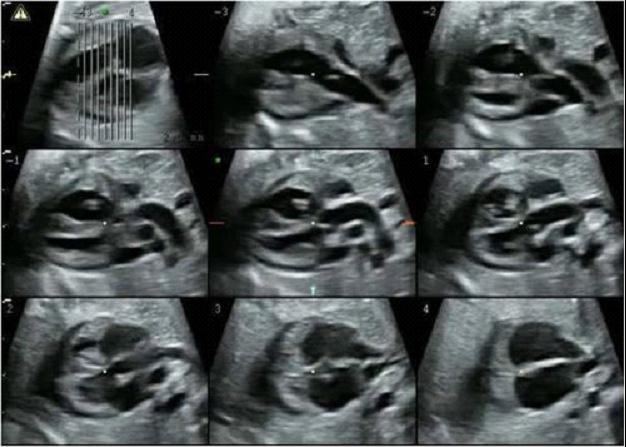

胎儿超声心动图,又称胎儿心脏超声扫描,是指利用医用超声波扫描设备,经孕妇腹部,系统检查胎儿心脏及大血管结构、节律和功能的临床诊断技术。

(4)胎儿心律失常。胎儿心动过缓(心律低于100次/分),心动过速(大于200次/分),持续心律不齐。

胎儿超声心动图检查的合适时间?

孕20-30周之间